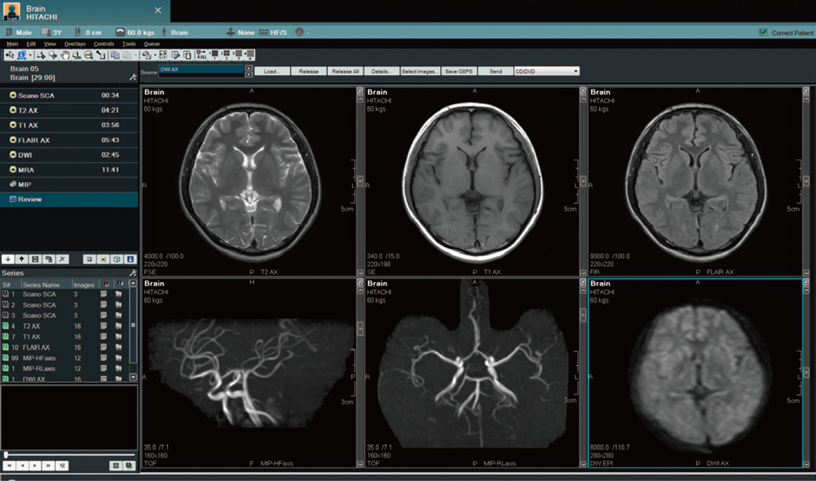

A soft celadon-based colour set, has been adopted for the GUI (Graphical User Interface). MRI imaging parameters that can be complex are more easily displayed on the Windows-based wide screen.

Routine protocols can be easily registered and changed by the operator, even during the examination to optimize the settings according to the patient and clinical requirements.